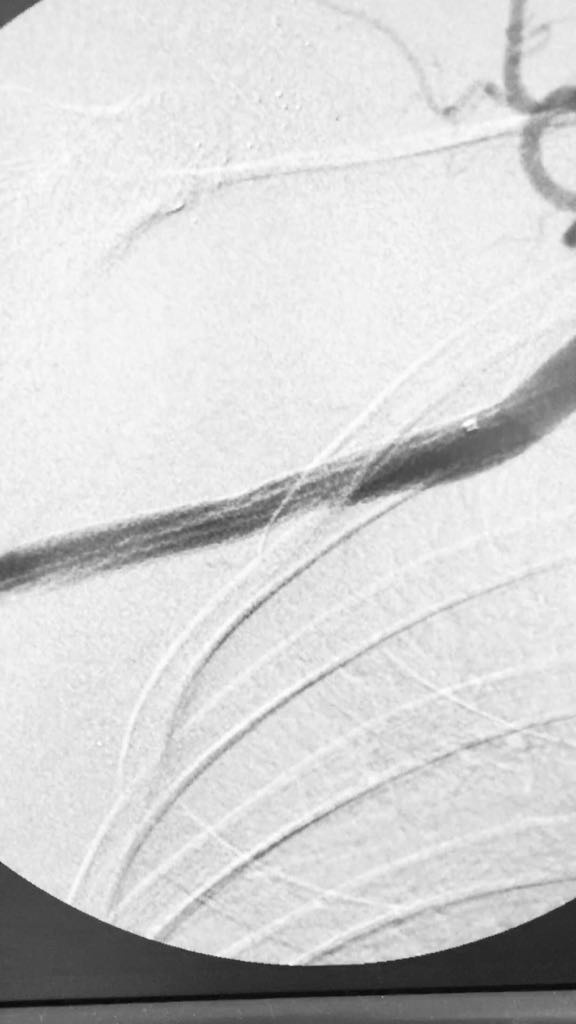

Somos una empresa enfocada en la atención en salud humana por medio del uso imágenes para ver diagnosticos y tratamientos de las diversas patologías con el uso de técnicas mínimamente invasivas en el territorio colombiano en el sector público y privado en búsqueda de una atención oportuna y de calidad a cada uno de nuestros pacientes.